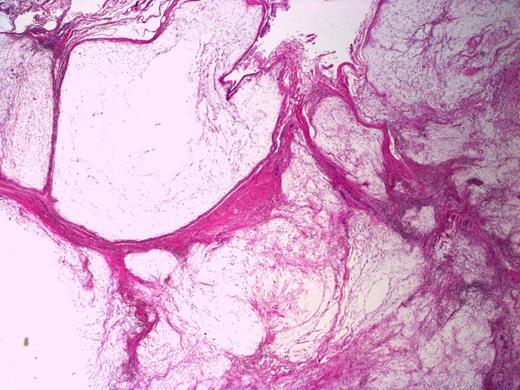

Sections of the lesion showed dense fibrous tissue with nodules of extracellular myxoid material containing scattered histiocytes and stellate to spindled fibroblastic cells. There was no evidence of necrosis, atypia or malignancy; this was consistent with Juxta-articular myxoma. (Figure 4 and 5). At one year follow-up there has been no sign of recurrence.

Bland spindled to stellate fibroblastic cells in a myxoid background. Note the surrounding septa composed of fibrous tissue. H&E stain, 200X magnification